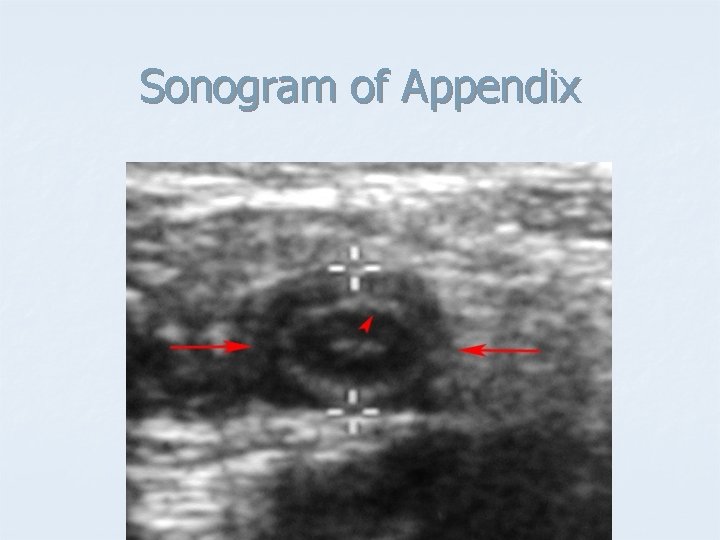

Sonogram of Appendix